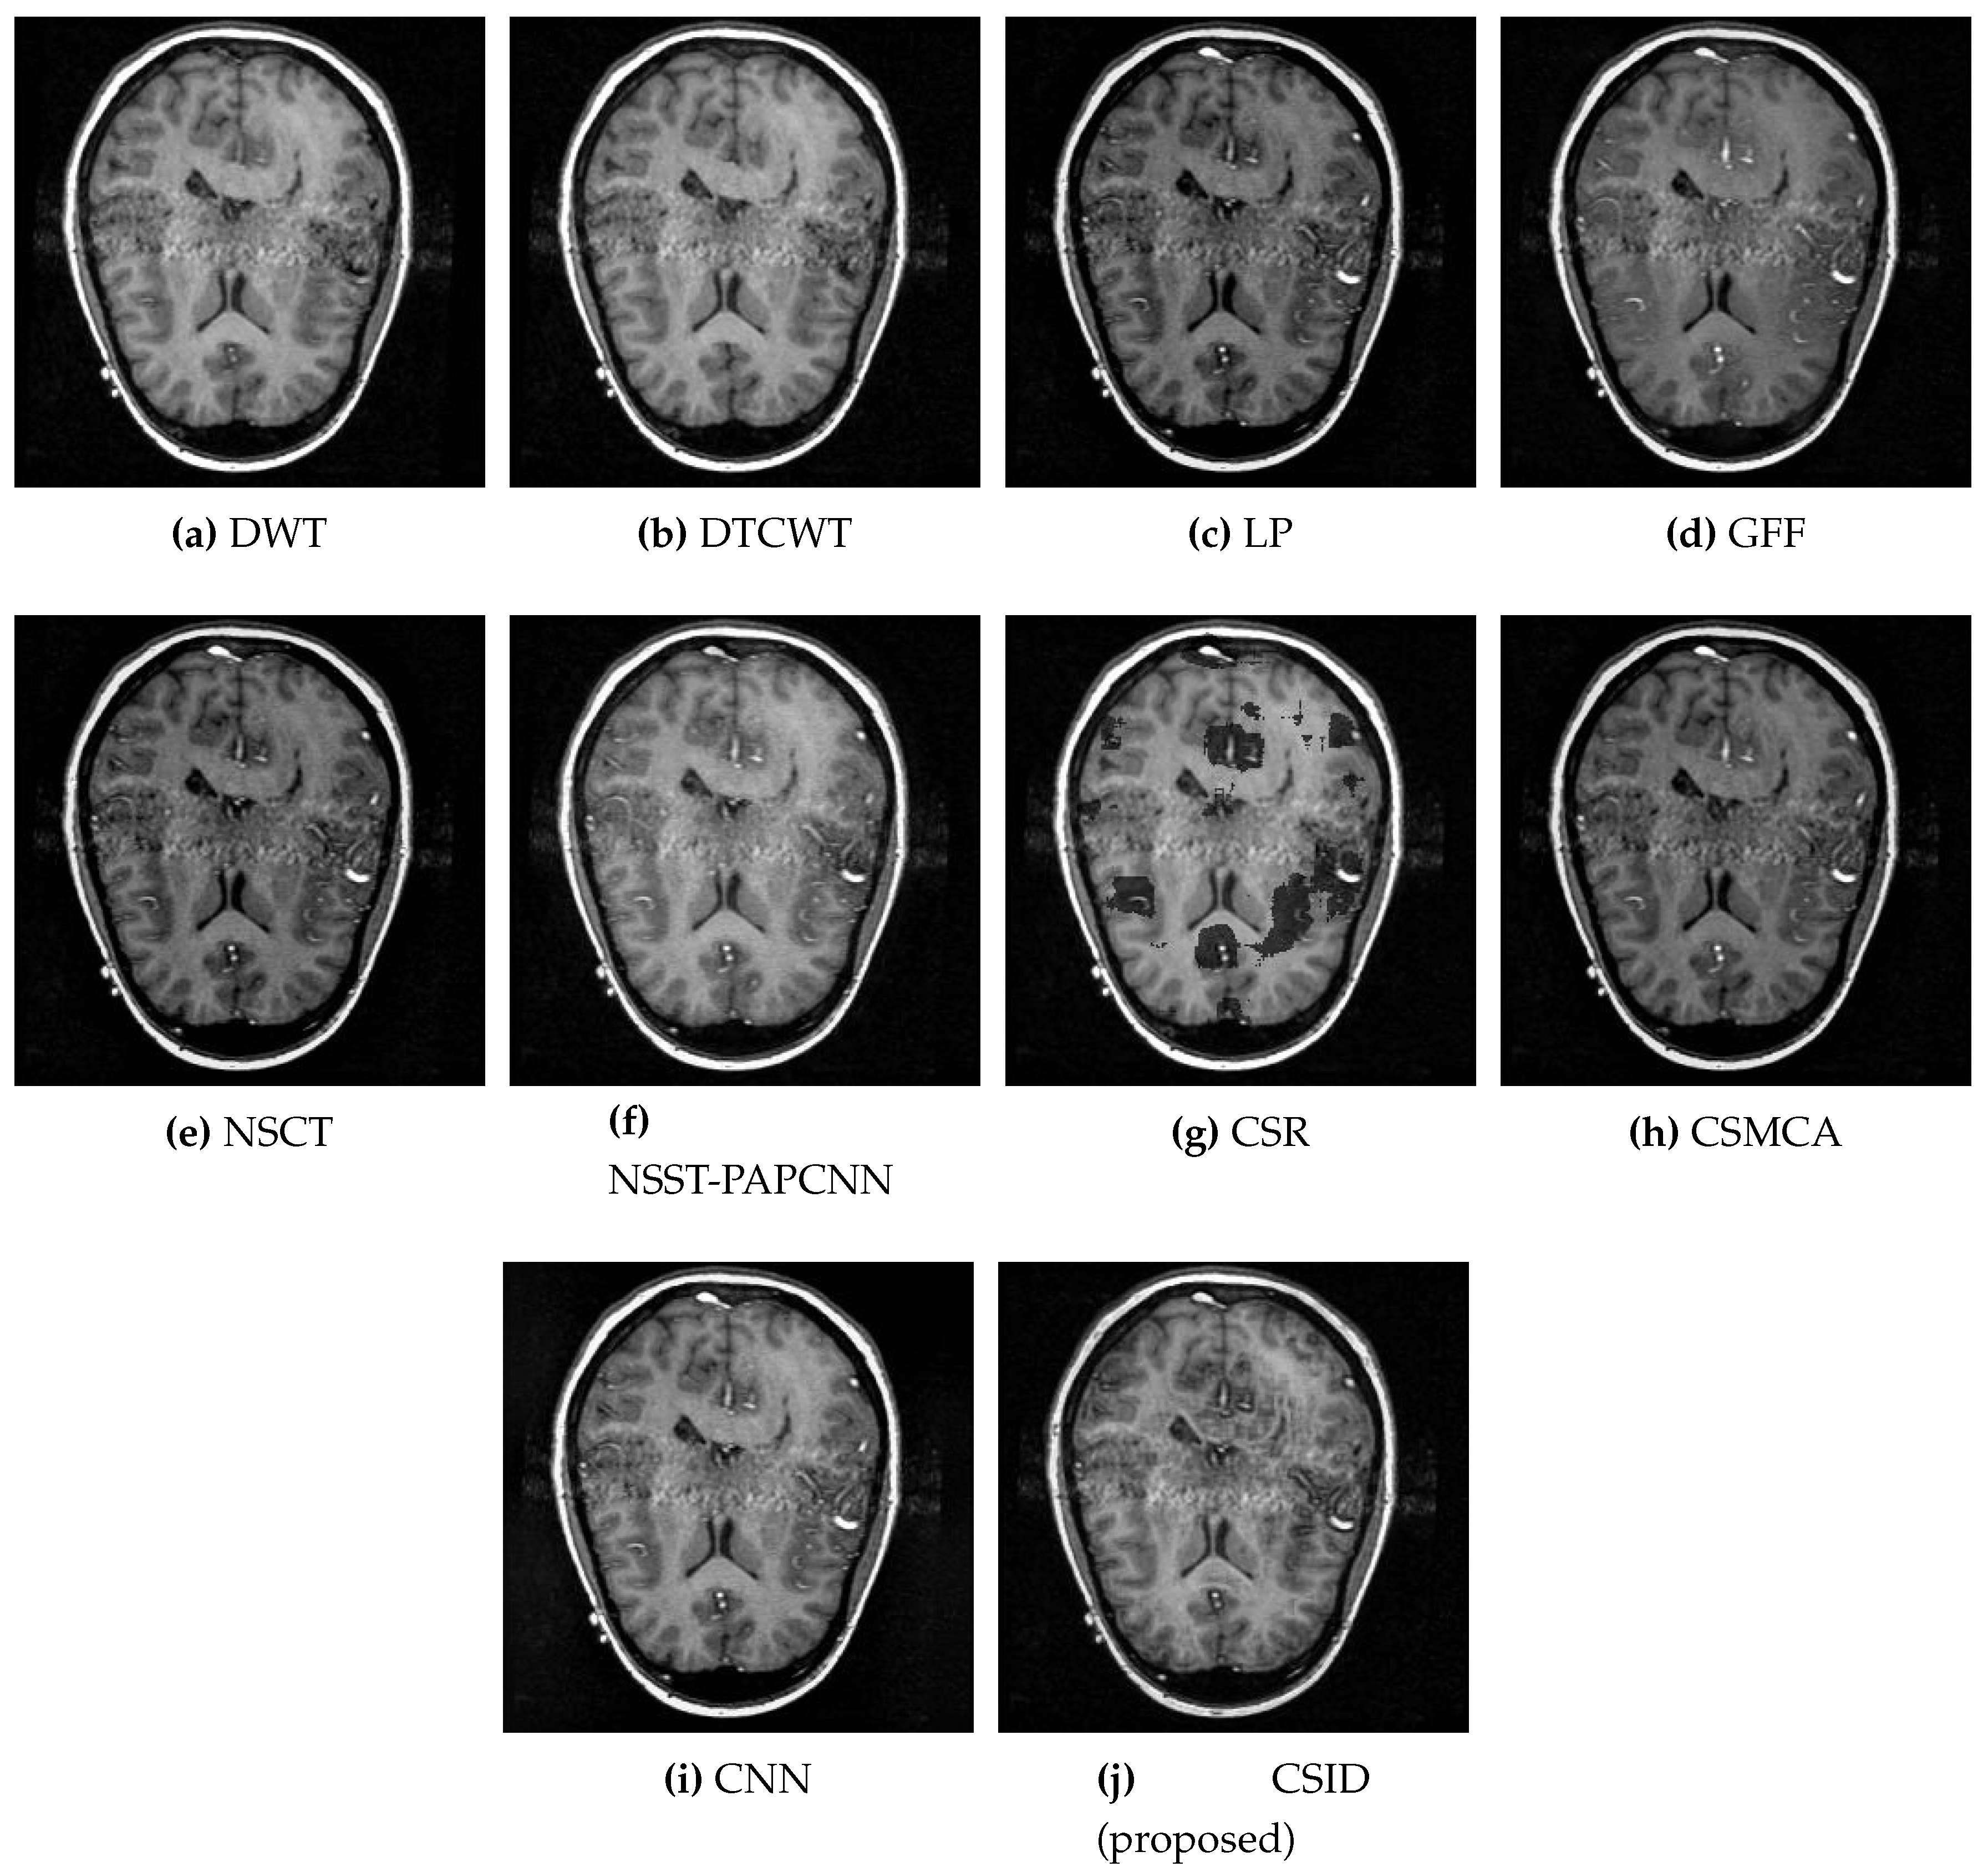

Finally, CSID and the aforementioned set of algorithms are evaluated using the Data-6 dataset, where Figure 10 demonstrates the corresponding qualitative results. All the algorithms, other than CSID, are unable of extracting detailed information that results in blurred fused images. To this end, our proposed CSID algorithm shows improved edge detection and provides enhanced contrast, in comparison with all the aforementioned algorithms that yield better visualization.

Figure 10. Comparative analysis, based upon visual observation, of the resultant fused images generated by the given set of algorithms using Data-6 dataset.

Diagnostics 10 00904 g010